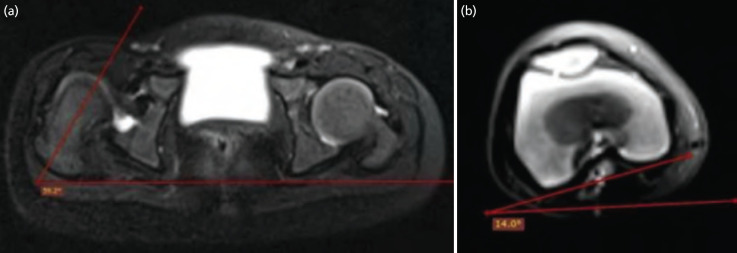

Material and methods: A prospective cohort study was conducted in unilateral idiopathic DDH cases those who underwent an open reduction in the age group of one to four years. Pre- and post-operative MRI was done to assess various acetabular and femoral parameters. Intra-operatively, osteotomy was planned. Based on stability assessment given by Zadeh et al Clinical follow-up assessment was done at three- and six-month post-op. Functional assessment using Modified McKay's criteria was done at six months follow-up.

Results: Out of 15 cases, seven children underwent only open reduction (OR), whereas eight underwent OR with Salter's osteotomy. Based on pre-op acetabular index and anteversion, Salter's osteotomy should be done in 14 out of 15 cases, but intra-operative stability test precluded Salter's in 6 cases. Post-operative anterior sectoral angle and femoral head coverage percentage were better in OR with Salter's group than OR-only group, but not statistically significant. Functional assessment at final follow-up showed all OR with Salter's group cases were Grade I, whereas in OR-only group, 4 were Grade I and 3 were Grade II.